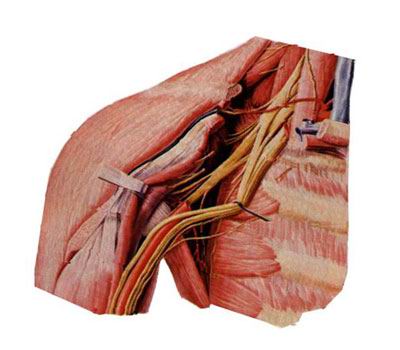

由第5~8颈神经前支、第1胸神经部分前支组成。 From 5 to 8 cervical nerve anterior branch, the former first thoracic nerve partially branched components. 穿斜角肌间隙,经锁骨后方入腋窝。 Wear scalene gap, the clavicle behind the armpit. 分为外侧束、内侧束和后束。 Into the lateral beam, the inside of the beam and rear beam. 主要分支有: The main branches are:

(1)肌皮神经 (1) musculocutaneous nerve

由臂丛外侧束发出,沿肱二头肌深面下行,肌支支配前臂前群肌,皮支布于前臂前外侧半皮肤。 Issued by the brachial plexus lateral beam, deep surface downstream along the biceps muscle group supporting former dominant forearm muscle, cutaneous branch of the cloth in half before the lateral forearm skin.

(2)正中神经 (2) the median nerve

由来自于外侧束和内侧束的两个根合成,伴肱动脉下行至肘窝,在前臂前群肌深浅两层之间下降,经腕管入手掌。 Synthesized by two roots from the inside to the outside of the beam and the beam, with the brachial artery down to the cubital fossa, a decrease in muscle depth between the two groups before the forearm, the carpal tunnel into the palm of your hand. 肌支主要支配前臂大部屈肌,皮支主要布于手掌桡侧三个半指及相应手掌皮肤。 Muscular branches mainly dominated most of the flexor forearm, cutaneous branches mainly distributed in three and a half refers to the radial side of the palm and palm skin accordingly. 损伤后表现为“猿手”。 After the injury manifested as "ape hand."

(3)尺神经 (3) of the ulnar nerve

由臂丛内侧束发出,初伴肱动脉下降,继而绕过尺神经沟至前臂伴尺动脉入手掌。 The inside of the beam emitted by the brachial plexus, brachial artery with early fall, and then bypass the ditch to the ulnar nerve ulnar artery forearm with the palm of your hand. 肌支主要支配前臂尺侧一个半屈肌(尺侧腕屈肌和指深肌尺侧半,简称 一尺半深 )和大多数手肌。 The main branch of the ulnar forearm muscle dominate a half flexors (flexor carpi ulnar half and refers to the deep muscle, called a Chiban deep) and most of the hand muscles. 皮支主要分布手掌尺侧一个半指、手背尺侧二个半指及相应手掌、手背皮肤。 Cutaneous branch of the ulnar palm mainly refers to one and a half, two and a half back of the ulnar finger and the corresponding palms, back of the hand skin. 肱骨髁上骨折最易损伤尺神经,表现为“爪形手”。 Supracondylar fractures of the ulnar nerve injury prone, the performance of "claw hand."

(4)桡神经 (4) the radial nerve

由臂丛后束发出,沿桡神经沟下行至前臂及手背。 After the beam emitted by the brachial, radial nerve downstream along the ditch to the forearm and hand. 肌支主要支配臂和前臂后群肌及前群的肱桡肌。 Muscular branches dominate arm and forearm major muscle group and the former group of brachioradialis. 皮支主要布于手背桡侧两个半指及相应手背皮肤。 Mainly distributed in the dorsal cutaneous branch of the radial side of the two half-back means and corresponding skin. 损伤后表现为“垂腕”。 After the injury manifested as "vertical wrist."

(5)腋神经 (5) axillary nerve

由臂丛后束发出,绕肱骨外科颈行向后外,肌支支配三角肌,皮支布于肩部皮肤。 Beam emitted by the brachial plexus, around the surgical neck of the humerus back row, the deltoid muscle branch domination, cutaneous branches distributed in the shoulder skin. 损伤后表现为“方肩”。 After the injury manifested as "shoulder."